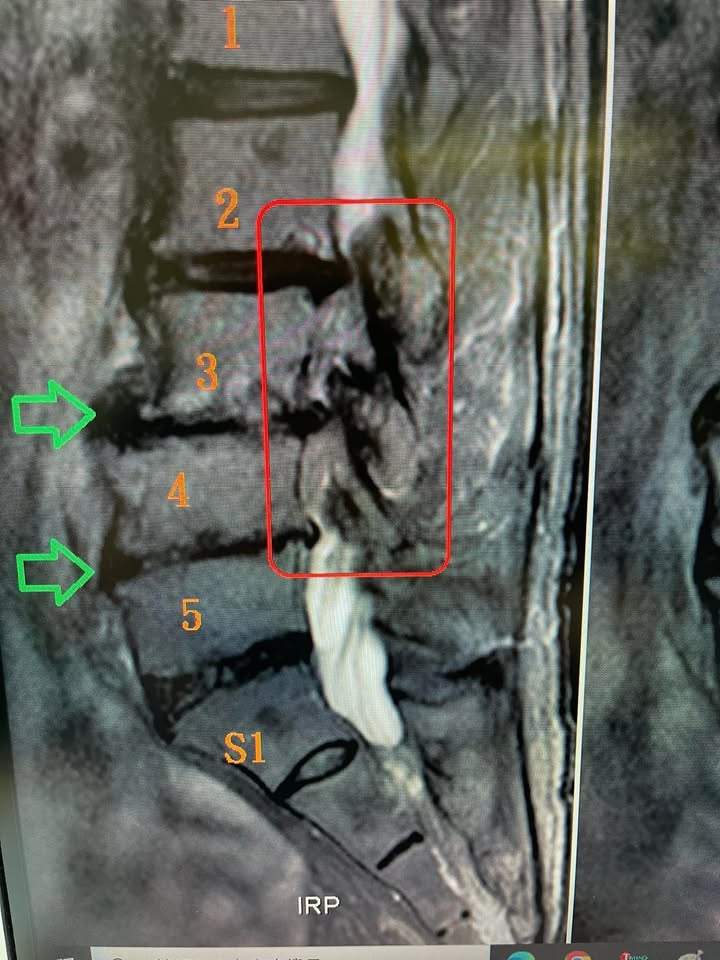

Cervical Spine Treatment Cases 腰椎治療案例 陳先生的選擇:從開刀邊緣到重新站起來 2025.06.11 ⭕️這不是奇蹟,是身體的智慧:12次脊椎微創針刀治療,換來椎間盤自然吸收的證據 鐵人選手的腰椎挑戰:椎管狹窄與筋膜治療的關鍵 2023.02.24 跌倒後坐骨神經痛?梨狀肌損傷與椎間盤突出的治療要點 2023.03.09 椎體滑脫與椎孔狹窄導致疼痛?如何有效治療與預防 2023.03.10 腰椎嚴重狹窄到走不到20公尺?6週內恢復走操場10圈的治療故事 2023.03.11 腰椎滑脫與狹窄導致走路困難?10週內重拾輕鬆步伐 2023.04.23 重度椎間盤突出導致腳麻痛?8週內改善的康復案例 2023.03.03 腰椎滑脫導致翻身困難?如何從晨起劇痛到輕鬆下床 2023.02.23 吃止痛藥10年無效?重度頸椎病患者的8週逆轉故事 2023.02.08 椎管狹窄合併腰椎滑脫?大醫院部長級醫師的8週逆轉故事 2023.01.19 腰椎管狹窄嚴重患者的康復奇蹟:8週內擺脫跛行 2022.12.21 工作受限、24小時疼痛?巨大椎間盤突出的快速康復案例 2022.12.20 腰痛痛到無法入睡?如何在2個月內擺脫折磨 2022.12.20 打籃球受傷後腰痛不斷?12週內快速改善的真實案例 2022.11.08 ← 上一頁 1 2 3 4 5 下一頁 →